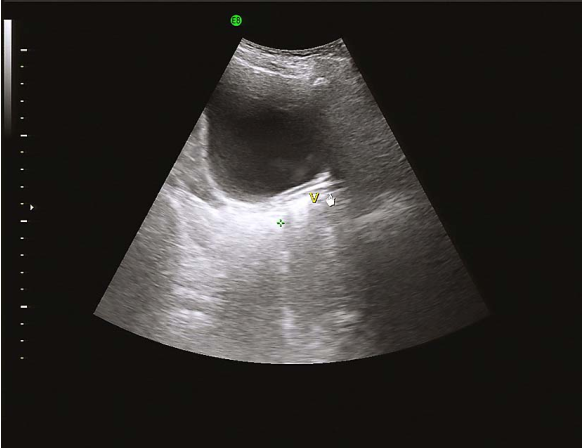

先天性无子宫经腹部超声